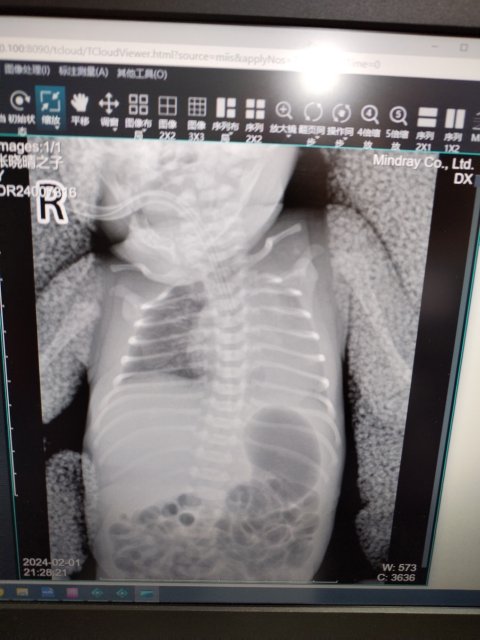

通过沟通,聂潘荣了解到,患儿出生后出现了重度窒息、全身水肿、重度贫血、黄疸等症状,并且床旁X片显示左肺发育不良,虽然腾冲市人民医院采取了气管插管有创呼吸机辅助呼吸等急救措施,患儿生命体征暂时稳定,但患儿所在医院无Rh阴性血,急需转诊。